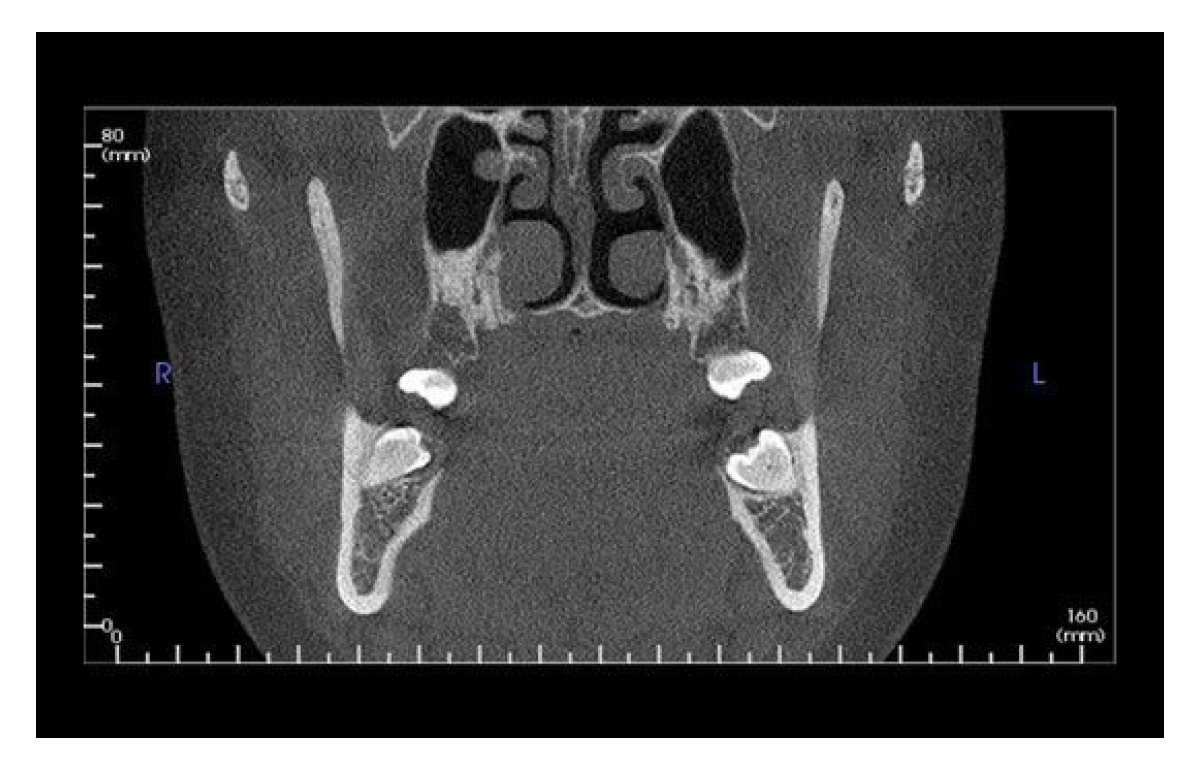

This dynamic system offers three maximum fields of view (FOV), V8, V10, and V17. Within these sizes, you also have the option to scale or collimate the scan height to capture only the area of interest per the patient’s immediate need. The system also provides enhanced low-dose imaging options through protocols and collimation, dedicated traditional 2D panoramic capabilities, and the feature-rich Tx STUDIO™ software.

The i-CAT FLX V10 combines highly precise cone beam 3D technology with flexible planning and treatment tools. The i-CAT offers a full suite of solutions to meet the needs of your practice. V10 scan sizes range from an adjustable 8cm x 5cm to 16cm x 10cm.

Designed to accommodate the widest range of clinical applications, the V17 is the most flexible of the V-Series options. This unit has a maximum and scalable FOV of up to 23 cm x 17 cm. The V17 is used most often by orthodontists, oral maxillofacial surgeons and oral radiologists.

Full 24.2 cm x 19.3 cm Sensor